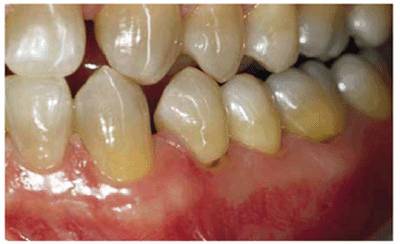

patient (Figures 17-1A to

C

Figure 17-1A to C: These photographs illustrate the complex dental condition of a 71-year-old male: (A) The palatal cervical regions of the maxillary anterior teeth exhibit sharp, wedge-like lesions that are characteristic of abfraction. These areas would be difficult, if not impossible, to have resulted from toothbrush abrasion. (B) The buccal aspects of the maxillary posterior teeth show smooth, concave configurations that are consistent with toothbrush abrasion and/or erosion. (C) The buccal surfaces of the mandibular teeth have lesions that possess components of both abfraction (sharp margins in the occlusal regions) and abrasion (concave geometry and gingival recession in the cervical regions).